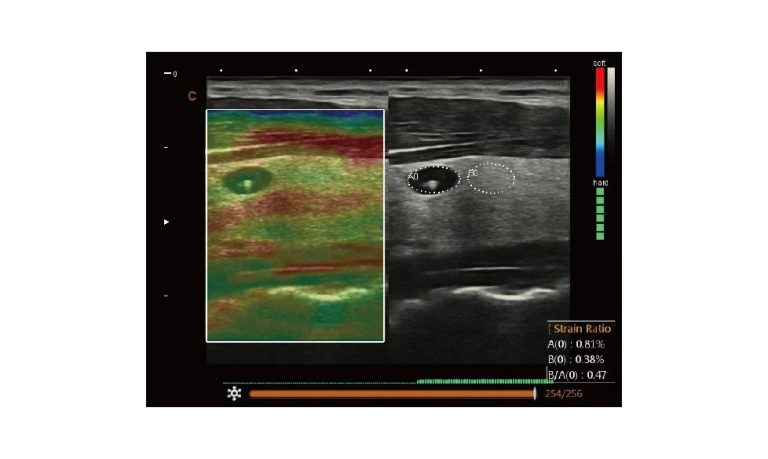

Ultrasound

Wide range of Ultrasound machines that suites a variety of applications from abdominal to rectal scans, we take in consideration how the world is moving towards mobility and mobile applications.

Esaote MyLab Sigma; So Fast, So Easy

Esaote’s new MyLab™SigmaVET is the smart, portable solution that allows use of an ultrasound whenever a quick and complete diagnosis is required.